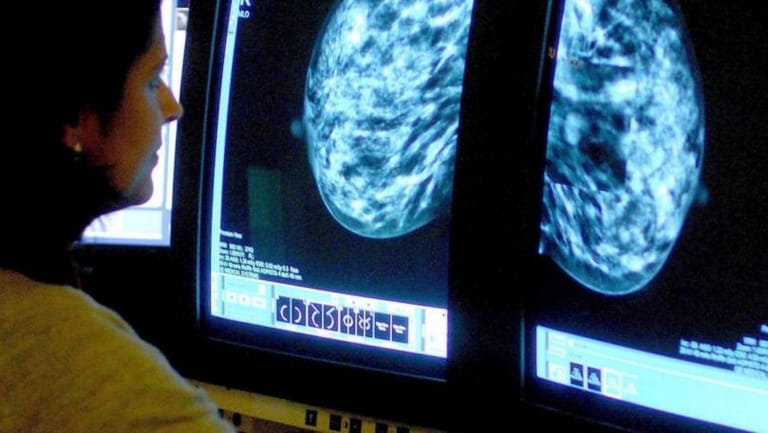

However, there are many actions people can take to reduce their risk of developing breast cancer. A breast screening, also known as a mammogram, is an x-ray picture of the breast used to check for breast cancer in women. A mammogram can detect otherwise invisible signs or symptoms of breast cancer that cannot be felt, or can check for breast cancer after a lump or other signs of breast cancer has been detected.